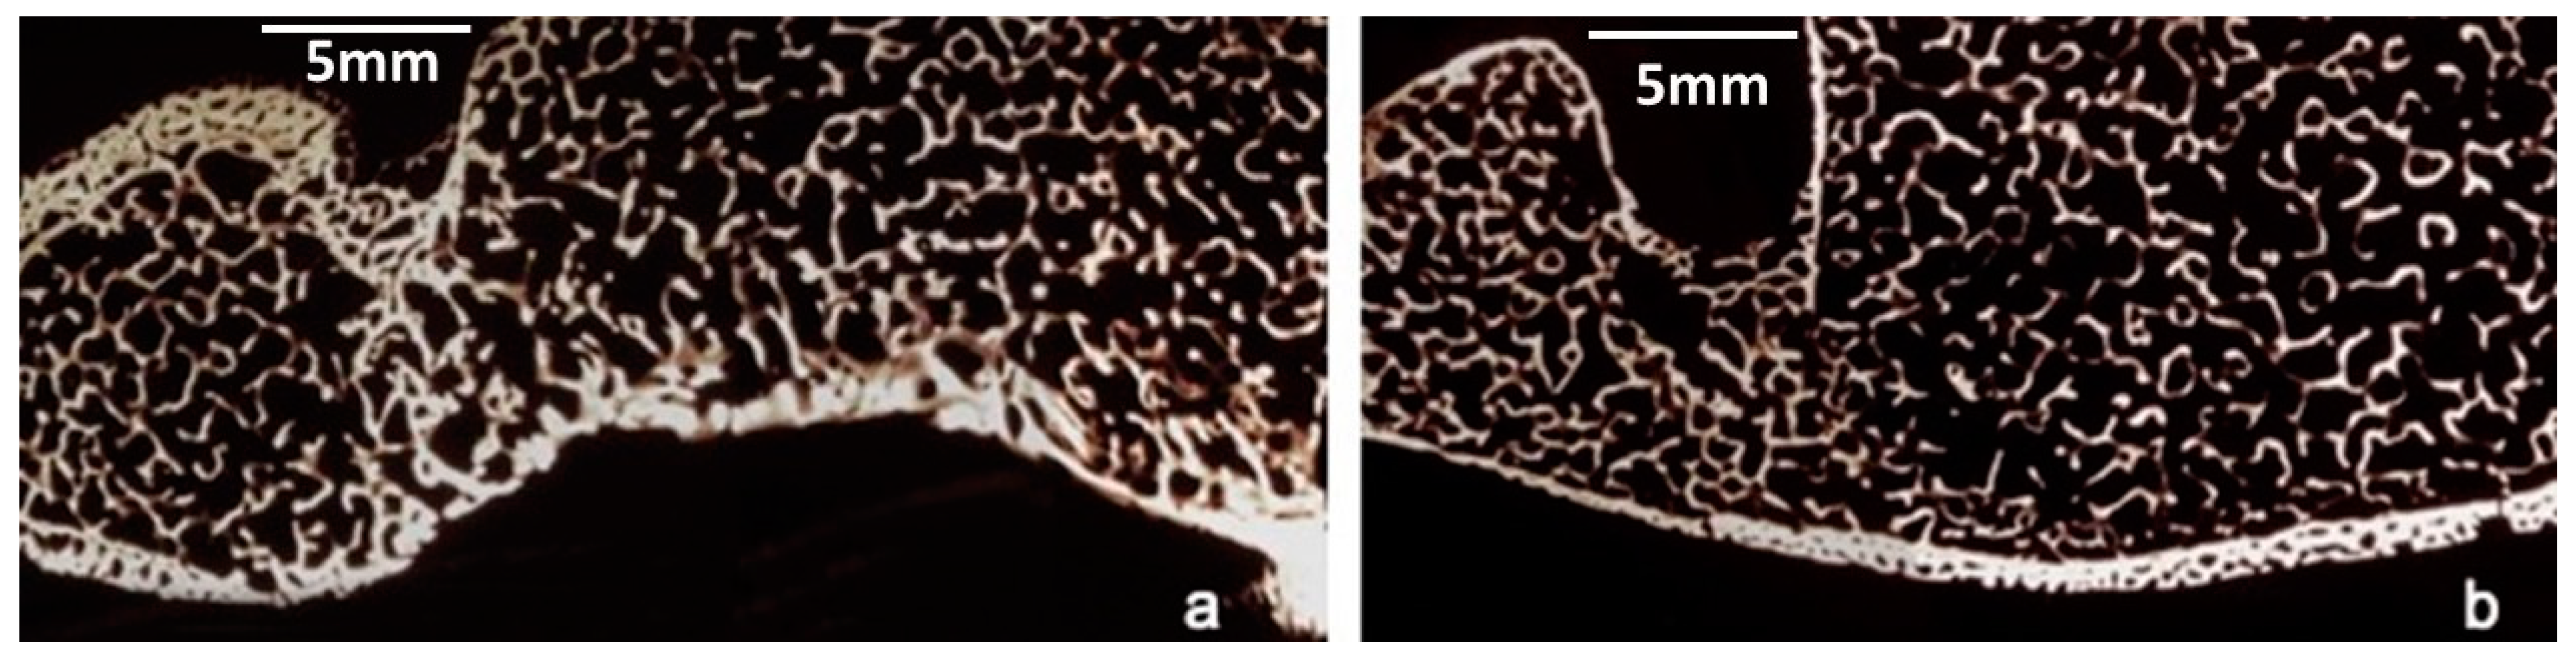

After 28 months, the histological examination of the 1st level of the right anterior flipper, removed after the animal’s death, showed mostly woven bone surrounding a wide medullary cavity with a thick layer of interposed fibrous tissue. Compact necrotic bone fragments could be identified inside the medullary cavity, showing numerous erosion cavities and surfaces (Figure 8a). No direct contact was observed between this necrotic bone and the newly-laid-down vital bone. The intermediate two levels (2nd and 3rd levels) presented three distinct tissues: vascularized woven bone, cartilage, and fibrous tissue. The newly-laid-down bone was often situated close to cartilaginous islands. These areas of cartilage tissue were densely populated with hypertrophic chondrocytes surrounded by a deep violet-stained capsule. A few large immature vascular cavities were observed within the cartilage next to the newly-laid-down bone (Figure 8b,c). At the 4th level, the primary bone formed an entire circular structure, in which a rough stratification was already appreciable. There were many large primary osteons presenting a thin, rather radio-opaque wall. The wide vascular channels of primary periosteal bone exhibited a prevalently radial direction, whereas in the internal layer the vascular channels were arranged longitudinally. Near the endosteum, secondary voluminous osteons were visible, delimited by evident cementing lines (Figure 8d). In some peripheral areas the cartilage was visible as a sheath surrounding the periosteal bone (Figure 8e). Fibrous tissue was observed at all levels.

3.3. Morphometric Findings

The diameters of the callus tissues were significantly larger than those of the control humerus diaphysis. In all the sections woven bone tissue neoformation was evident, though to a different degree at the various levels examined. At the proximal level (1st level), a complete bone sheath of compact, spongy tissue was present surrounding a wide medullary cavity, within which fragments of preexisting necrotic bone over extensive surfaces and with erosion cavities were clearly visible. On average, at the intermediate levels (2nd,3rd level) 20% of the space was occupied by compact bone with wide vascular channels, sometimes opening toward the periosteum, and 32% by cartilage, present largely on the medial side. Inside the medullary cavity there were still slight residues of preexisting necrotic bone. Finally, at the distal level (4th level), there was a complete compact bone sheath, partly stratified due to periosteal growth on preexisting bone portions, accounting for about 56% of the entire section. Moreover, in the preexisting bone, numerous secondary osteons could be seen (Figure 8f). The cartilage, which was sometimes calcified, extended over 6% of the surface, in a fairly thin layer confined to peripheral areas of the medial side of the callus. In the control bone the compact diaphysis occupied 74% of the section (Scheme 1).

Figure 8. (a) microradiograph of the first level: the bone fragment shows numerous erosion cavities (white arrows). (b) histological findings at 2nd level. Three distinct areas are evident: fibrous tissue, woven bone, and cartilage. The white arrows point to wide immature vascular cavities within the cartilage next to woven bone (toluidine blue). (c) histological findings at 3rd level: the microphotograph shows a cartilage area densely populated with hypertrophic chondrocytes surrounded by an evident capsule. These islands are adjacent to the newly-laid-down bone (toluidine blu). (d) microradiograph of the 4th level: the photo shows an entire circular structure presenting a rough stratification. The red asterisk indicates more central mineralized (radio-opaque) areas with many visible osteons; the white asterisk shows peripheric cartilage impressions. (e) Histological section of the 4th level: peripherally are visible cartilaginous islands surrounding primary bone (violet-stained) (toluidine blue). (f) microphotograph of the 4th level: In the internal mineralized areas, secondary voluminous osteons are evident. (Green arrow) (toluidine blu).